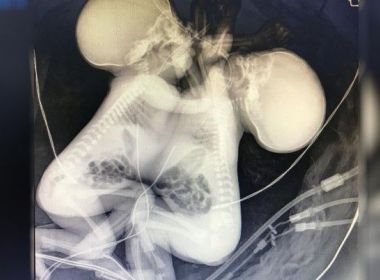

Casos recentes de gêmeos siameses em SAJ podem estar ligados a qualidade da água e solo

A incidência de gêmeos siameses, unidos em alguma região do corpo, é de um caso a cada 200 mil nascidos vivos, de acordo com o médico.